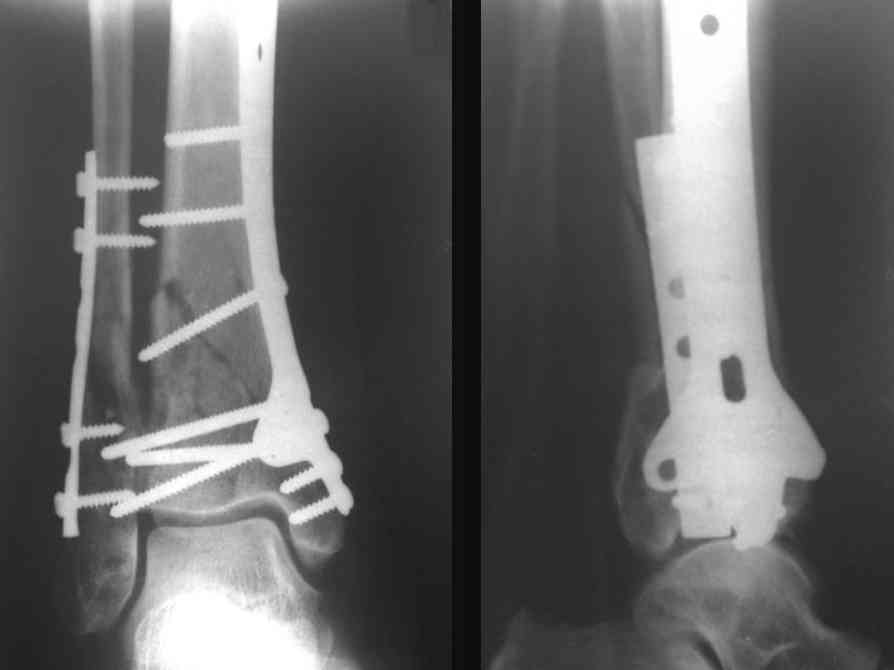

Послала ещё два снимка, если не пройдут, пошлю ещё. Дрягин. Если есть вопросы, готов ответить.

Посылаю результат лечения предыдущего больного через год.

С уважением Дрягин